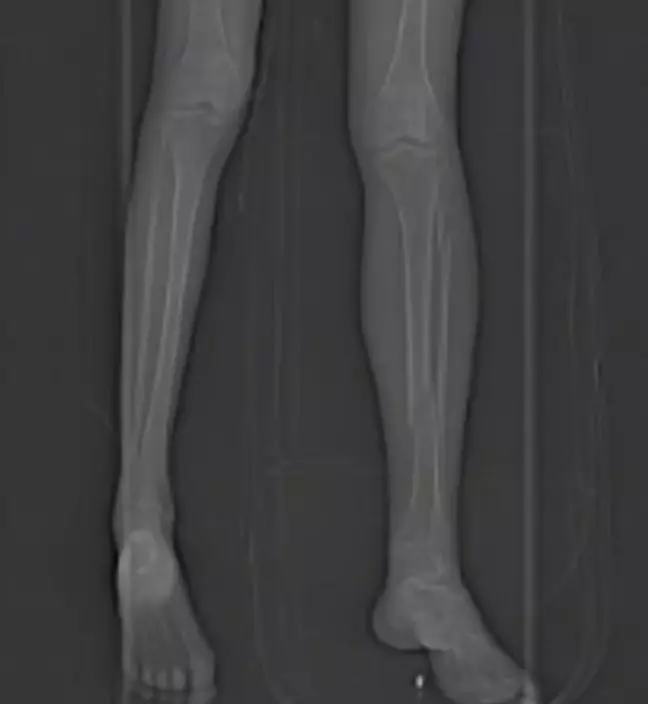

網民留言熱議

影片曝光後,不少網民批評該動作存在高度風險,「本來單板就容易造成腿部扭折,她還踩著一個人滑」、「這不是滑雪,是找危險」、「聽到聲音都覺得痛」、「想模仿動畫結果出事」、「為了拍片太拚。」也有網民以動漫梗調侃:「想 cos 銀魂吧?」、「骨折也是素材,流量有了。」片段末段更附有女子事後拍攝的 X 光片,證實骨折情況,並提醒觀眾切勿輕易模仿。